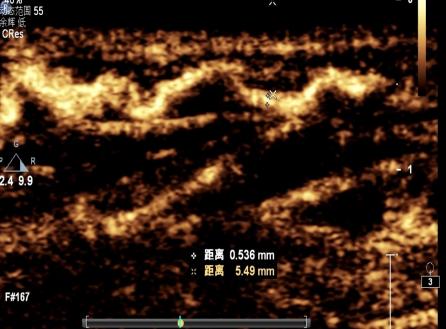

特色技術超聲醫學科設置有婦產、心臟、血管、腹部、淺表、介入、小兒超聲7個亞專業組。診療范圍覆蓋全部臨床超聲檢查和介入治療項目。開展產科三維超聲、經食管實時三維超聲心動圖、心肌應變定量分析、淋巴管超聲造影、肌肉骨骼及神經超聲、介入超聲治療、各類經皮、經導管心臟圍手術期超聲等特殊技術。

設備設施:擁有PHILIPS EPIQ CVx、PHILIPS EPIQ5、PHILIPS CX50、GE Vivid E95、GE Vivid E80、GE Voluson E10、GE LOGIQ E9、HITACHI Preirus等國內外先進的超聲影像設備。